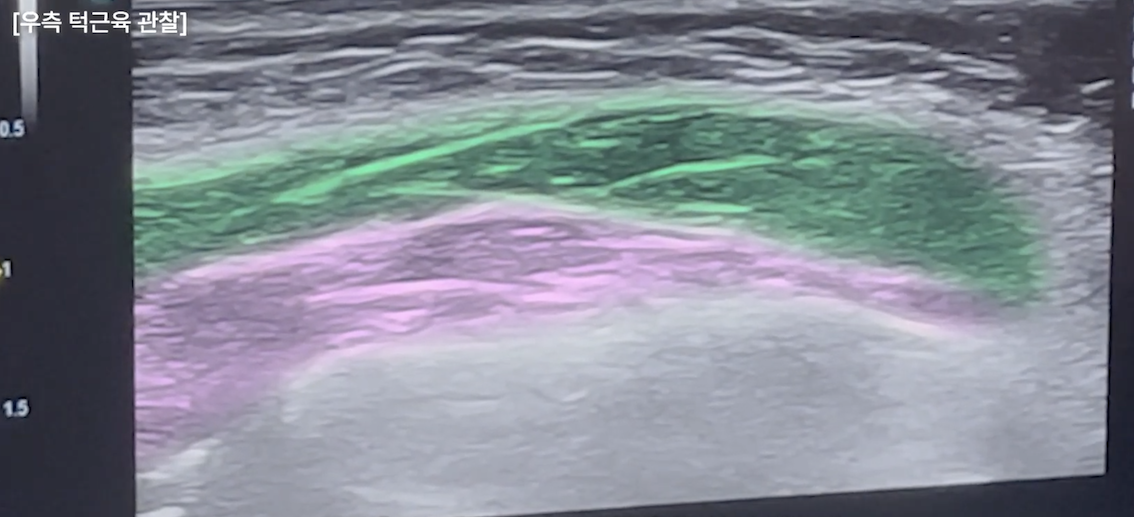

닉스의원 대전점에서는 보톡스 시술 시 초음파 영상을 꼭 보면서 하는데요.

특히나 턱근육은 해부학적으로 두 겹, 더 세분화하면 세 겹으로도 구분하는 근육이기에 각 근육층의 움직임을 확인해 정확한 근육층을 타깃으로 시술하는 것이 중요합니다.

앞서 설명드렸듯 교근은 총 세 겹의 근육층으로 이루어져 있습니다.

이를 꽉 물어보게 하면 어떤 층이 주로 작동하는지가 드러나는데, 이 차이는 손으로 만져서는 정확히 알기 어렵고 초음파로 직접 확인해야 명확해집니다.

거기에 턱 근육의 윗부분(광대부위)의 경우에는 턱 근육 위를 침샘(귀밑침샘)이 덮어 더욱더 볼륨을 형성하는 경우도 있기 때문에 초음파로 정확한 원인을 확인 후 시술하는 것이 중요합니다.

닉스의원 대전점에서는 초음파를 통해 가장 힘이 집중되는 근육의 핵심 포인트를 확인한 뒤, 그 지점을 정확히 겨냥해 시술을 디자인합니다.

또한 좌우 교근의 두께를 비교함으로써 어느 쪽에 용량 조절이 필요한지 판단할 수 있고, 정면에서 얼굴 한 쪽이 더 커 보이는 이유 역시 구조적으로 설명하고 교정할 수 있습니다.